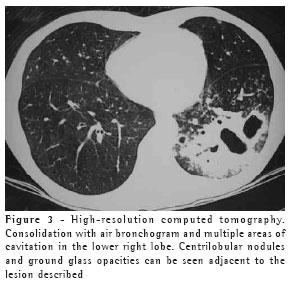

The most frequent finding in the imaging, present in the seven patients, was ill-defined consolidation (Figures 1, 2, 3 and 4). Five of patients presented air bronchogram, principally at the periphery of the lesion. In three cases, the consolidation was organized in the form of a mass. In six of the seven patients, irregular areas of cavitation were observed within the consolidations. Multiple cavitations were seen in five patients, and a singular cavitation was observed in one patient. In the patient presenting no cavitation, there were hypodense areas suggestive of necrosis (Figure 5). Only one of the patients presented air-fluid levels within the cavities.

Cavitated lesions predominated in the upper lobes, four in the right lobe and one in the left lobe. In one patient, the middle lobe was also affected. In two cases, such lesions occurred in the lower lobes, one in the right lobe and one in the left lobe. In four cases, the lesions affected only the lobes mentioned above and were therefore unilateral. In the remaining three cases, the contralateral lung was also affected, albeit to a lesser degree. In one case, there was also relatively thin-walled, multiloculated cavitation, without an air-fluid level, in the middle lobe.

Ground glass opacities, primarily surrounding the cavitated lesions, were reported in six patients, although this was not the predominant finding in any of the cases.

Small centrilobular nodular opacities presenting a 'tree-in-bud' pattern, predominantly encircling the area of consolidation, were observed in three patients. In one of those patients, the lesions were also found in the hanging portions of the lower lobes. Peribronchial nodules, tending toward confluence and located in the periphery of the pulmonary consolidations, were observed in four cases.

In our study, the principal pattern of pulmonary involvement was air bronchogram and cavitation, which was present in six patients. There were multiple cavitations in five cases and a singular cavitation in one. The consolidations were large and had irregular contours. The air bronchograms were located in the peripheral portions of the lesions. The pulmonary lobe most frequently involved was the upper right lobe, which was affected in four patients. Most of the case review studies confirm these findings.(2,5) Some studies have reported that, although cavitation might not be present at the time of diagnosis, it develops over the course of the disease.(4) In the sample evaluated in the present study, air-fluid levels within the cavitations were seen in only one patient.

Other findings were ground glass opacities, peribronchial nodules, small nodules of predominantly centrilobular distribution, and the "tree-in-bud" pattern. These alterations were predominantly seen surrounding the cavitated consolidations. In one case, they were also present in both of the lower lobes. It is believed that this finding indicates bronchogenic dissemination of the infection.